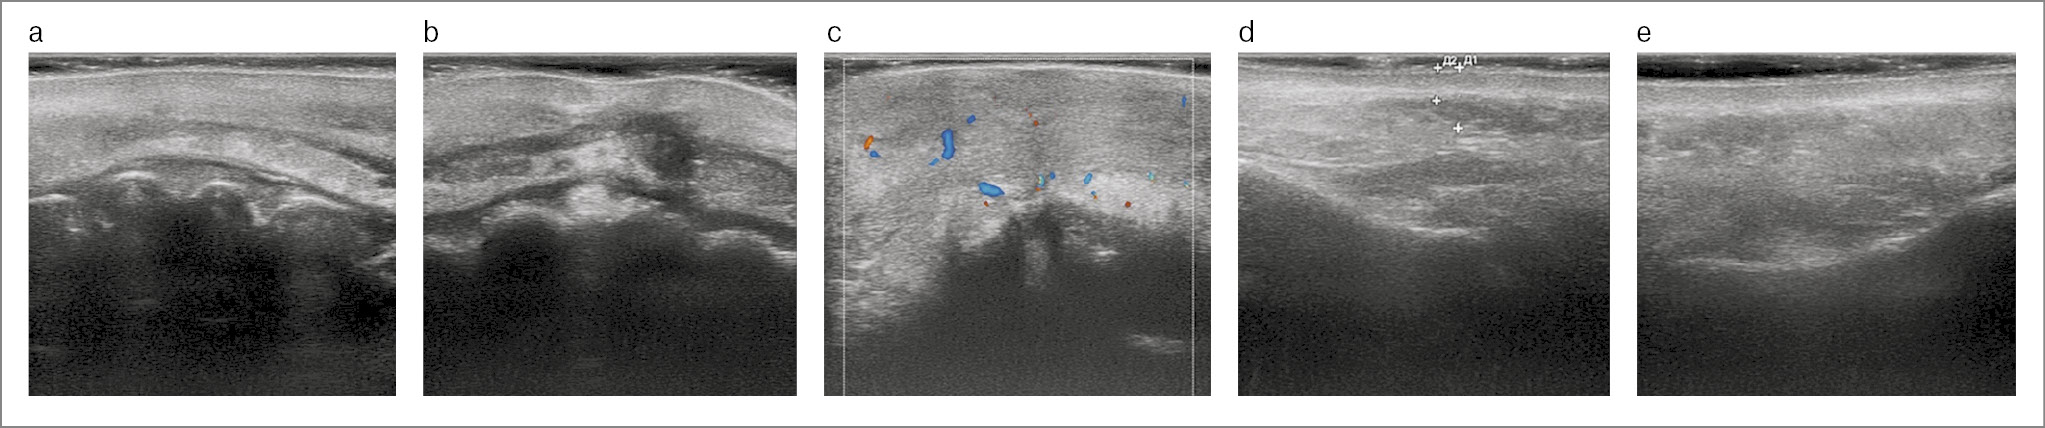

По данным УЗИ первичного приема в области кожной части верхней губы ткани плохо дифференцированы, визуализировалось гипоэхогенное образование – предположительно филлер, на основе ГК на глубине 2 и 3 мм диаметром от 6,6 до 2,8 мм, расстояние от поверхности кожи до круговой мышцы рта – 3,7 мм (рис. 2, а). В проекции колонн фильтрума на глубине 2,6 мм определялось гипоэхогенное образование общим диаметром от 4 до 6 мм, признаки внутрисосудистого компонента иникапсуляции отсутствовали, ультразвуковая картина соответствовала интерстициальному внутритканевому отеку (рис. 2, b). В области слизистой верхней губы имелись ультразвуковые признаки фиброзных изменений и нарушений васкуляризации, ткани плохо дифференцированы, слизистый и подслизистый слои отчетливо не визуализировались, присутствовали фрагменты анэхогенных включений (рис. 2, c). В области правой носогубной складки на глубине D1 (3,1 мм) и D2 (6,2 мм) определялись анэхогенные образования диаметром 17,3 и 15,3 мм соответственно с признаками инкапсуляции – усиления эхогенности по периферии. Слои кожной ткани плохо дифференцируются. Глубина нахождения образований (филлера) – средние слои дермы, субдермально (рис. 2, d). В области левой носогубной складки филлер визуализировался на глубине 2,3 мм, имел диаметр до 15,5 мм, ткани дифференцированы: толщина эпидермиса – 0,3 мм, сосочкового слоя дермы – 0,99 мм, сетчатой дермы – 1,2 мм, кожи над филлером – 3,4 мм (рис. 2, e).

Рис. 2. УЗИ первичного приема: а – область кожной части верхней губы; b – проекция колонн фильтрума; c – область слизистой верхней губы; d – область правой носогубной складки; e – область левой носогубной складки.